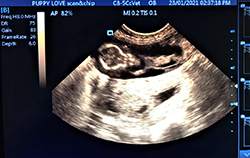

Mobile Ultrasound Pregnancy Scanning and Microchipping Services

Puppy Love scan and chip